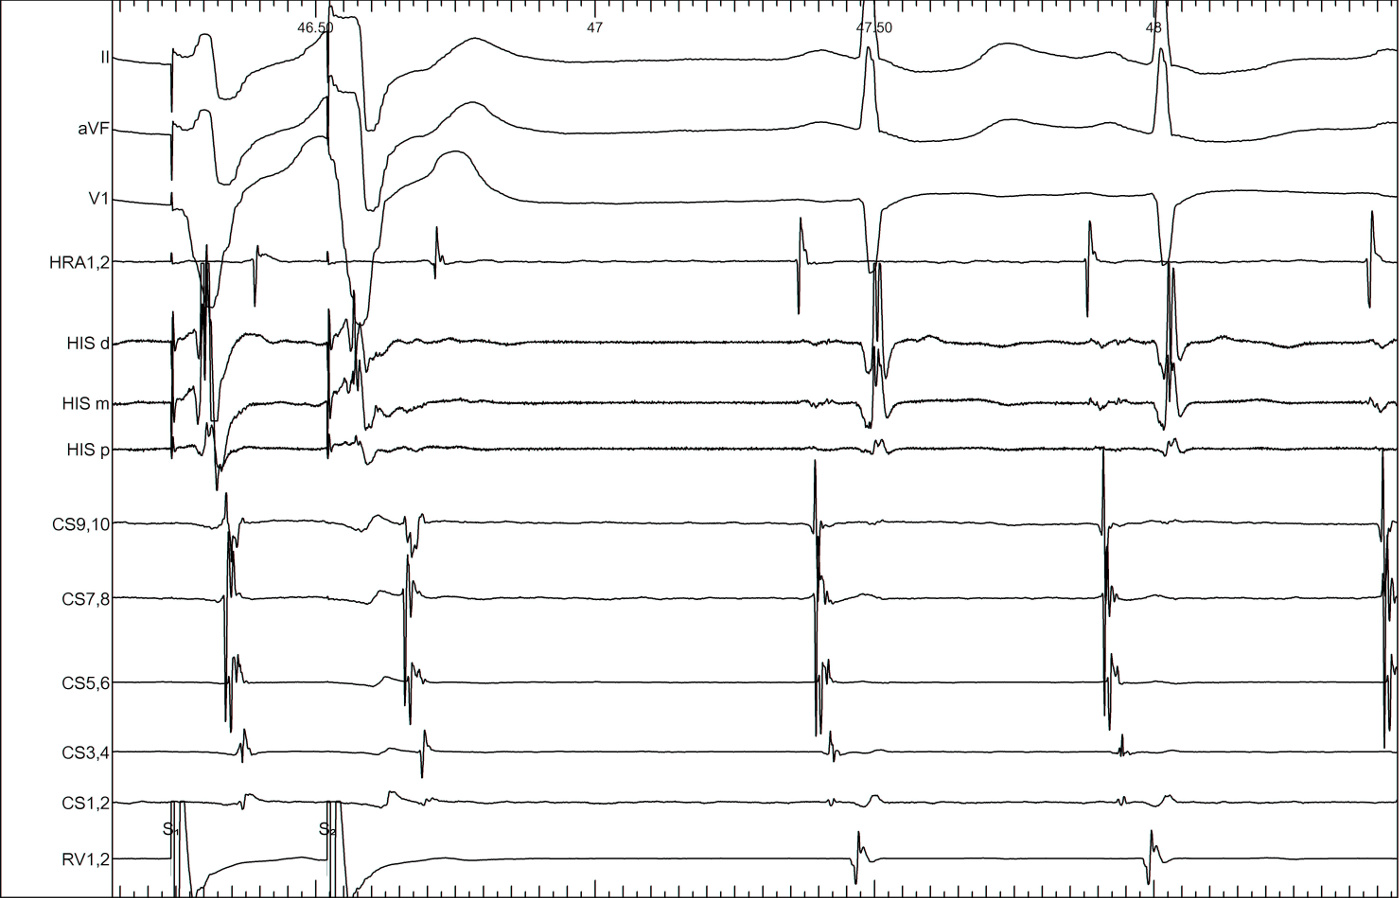

Bundle branch block

lbbb_narrow.jpg

lbbb_narrow_measurements.jpg

coumel.jpg